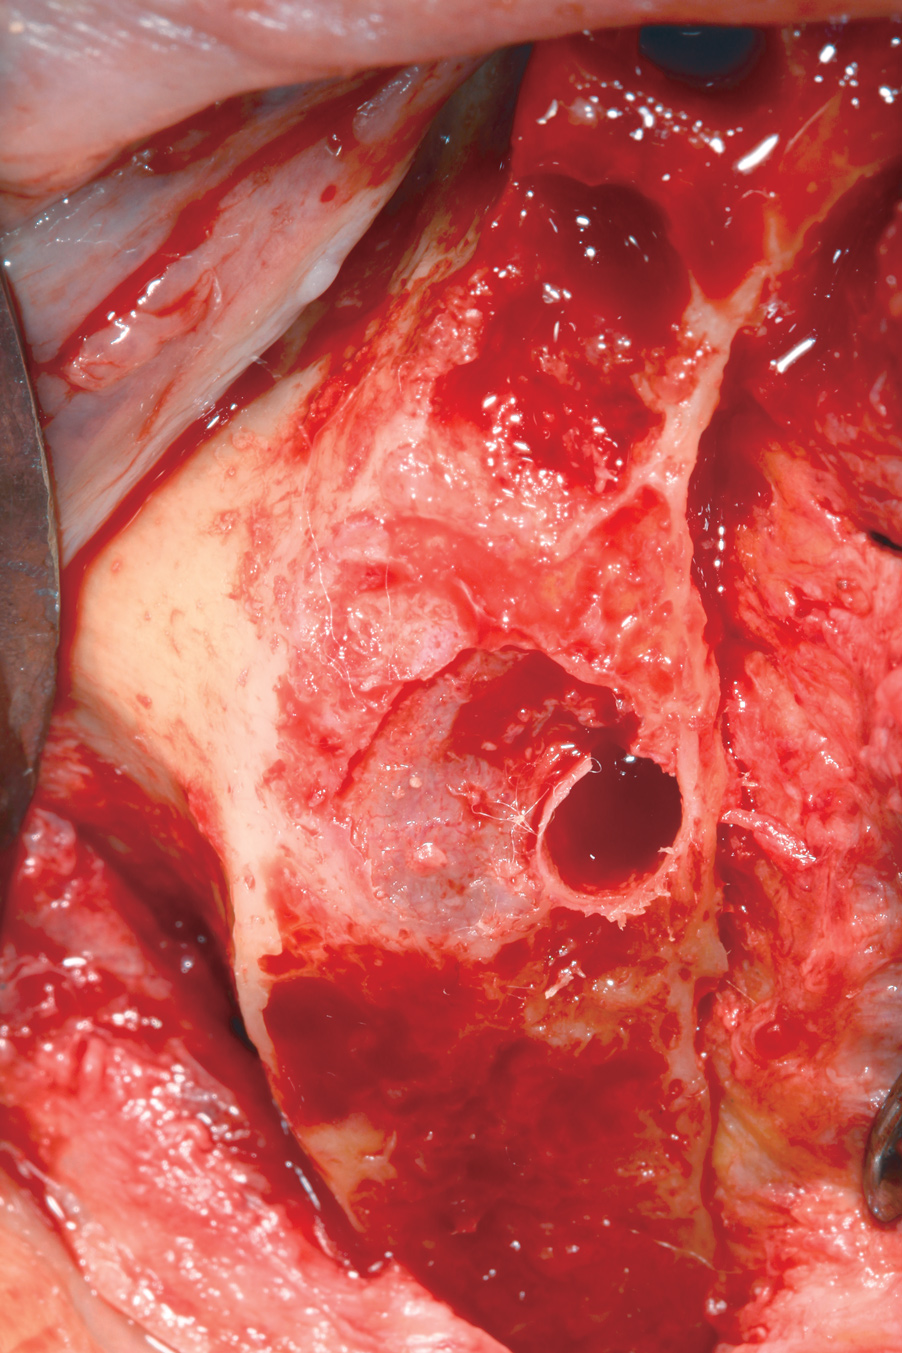

Hemorrhage From Osseous Nutrient Canals

All-on-4–style treatment typically involves reduction of alveolar and/or basal bone (Figure 9) to achieve adequate restorative space for both the interim and final prostheses.25-27 During reduction of this bone, exposure of intraosseous nutrient canals28,29 may lead to hemorrhaging that may obscure visualization of the surgical field. If left uncontrolled, hemorrhaging from nutrient canals can become significant, resulting in excessive blood loss. It is not uncommon to encounter multiple concurrently hemorrhaging intraosseous nutrient canals, especially during mandibular bone reduction.

When faced with this situation, the author uses the blunt end of a handheld instrument, such as a Woodson instrument (Figure 10), to put heavy pressure on bone directly adjacent to the bleeding nutrient canal. This pressure typically deforms the adjacent bone to a point at which it occludes the hemorrhaging. The author has encountered hundreds of hemorrhaging intraosseous nutrient canals and has never had this technique fail to achieve the desired results.

Fig 9. Alveolar bone reduction prior to dental implant placement in a mandibular All-on-4–style dental implant surgery.

Figure 9

Fig 10. Woodson hand instrument used to condense bone at the site of an intraosseous nutrient canal hemorrhage.

Figure 10